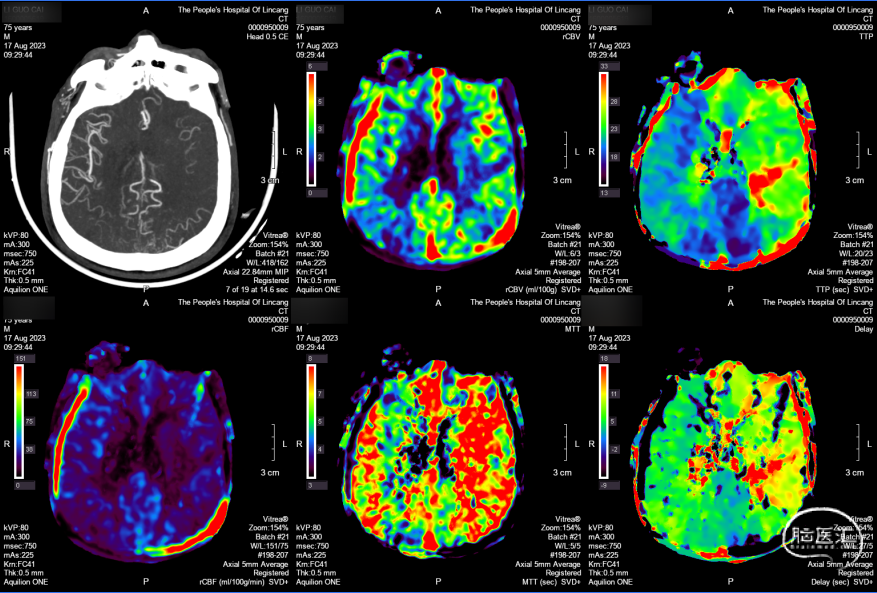

CTP:左侧大脑半球大面积TTP及MTT延长,CBV左侧大脑半球大面积TTP及MTT延长,rCBV基本正常或轻度下降,rCBF下降,符合脑梗死前期Ⅱ1期表现。